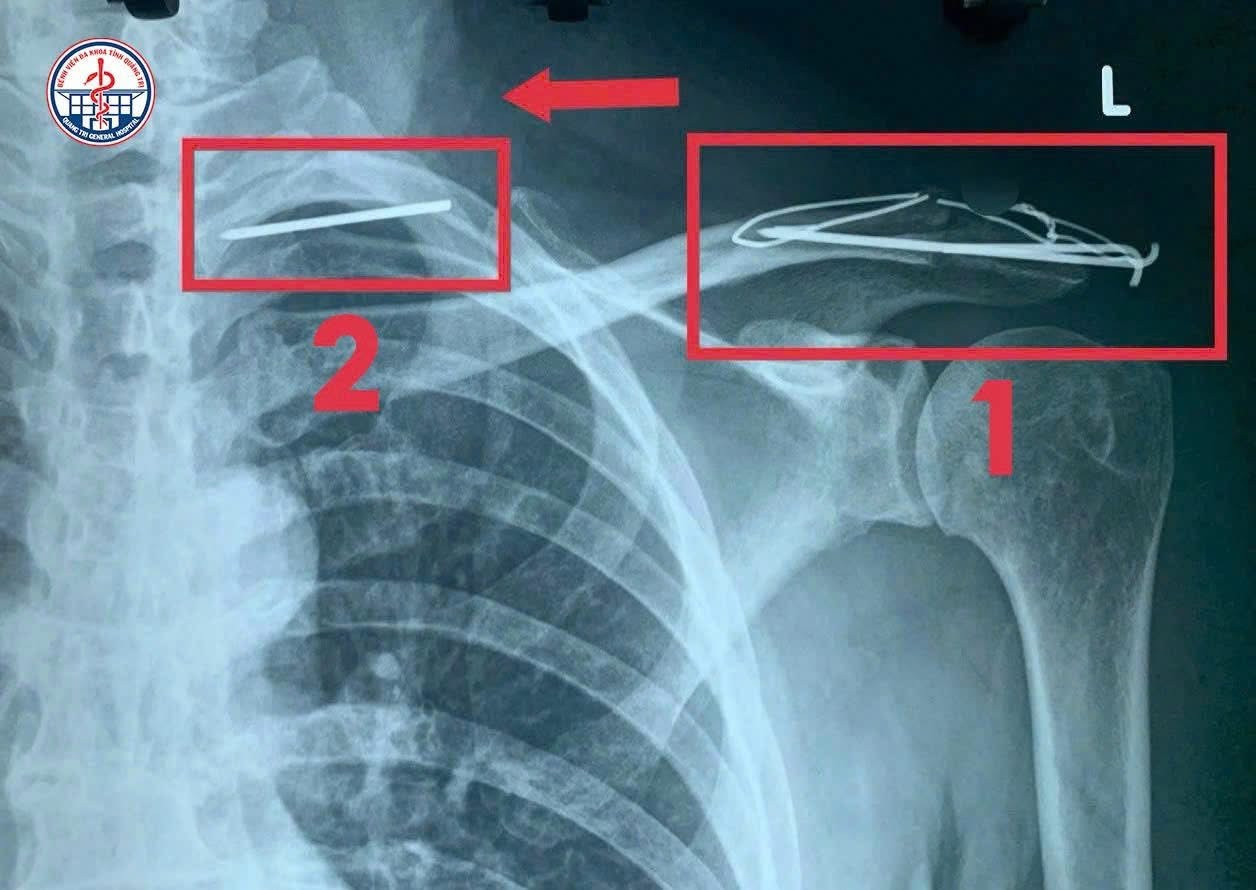

Phần đinh bị gãy di trú từ vị trí 1 sang vị trí 2 và đe doạ tính mạng bệnh nhân.

Kết quả chụp CT cho thấy, chiếc đinh bị gãy và di trú khắp lồng ngực bệnh nhân.